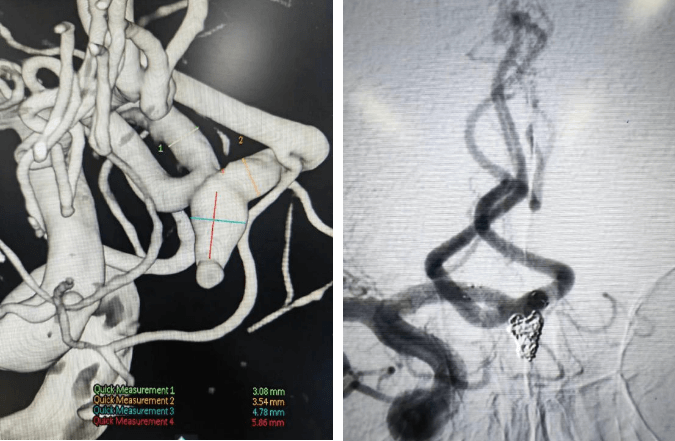

支架輔助動脈瘤栓塞術前、術后對比

術前血管畸形及介入治療后血管畸形消失(治愈出院)